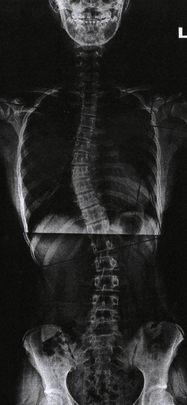

척추측만증(척추옆굽음증)

정상적인 척추는 정면에서 보았을 때 반듯하게 골반 위에 얹혀져 있어야 합니다.

하지만 반듯해야 할 척추가

S자나 C자 모양으로 휘어지는 증상과 동시에 척추 마디마디가 회전하여 틀어지는 변형을 함께 동반

하기도하는데 이러한 척추의 변형을

‘척추측만증’

이라고 합니다.

보존적 치료

운동치료를 통해 잘못된 자세교정 및 몸의 균형을 잡습니다. 만곡이 20도보다 작으면 3∼4개월마 다 정기적인 관찰이 필요하고, 20∼40도는 보조기를 착용하는 치료가 필요합니다.

수술적 치료

만곡이 40도 이상인 경우에는 척추고정술을 통해 수술적인 치료를 시행합니다.